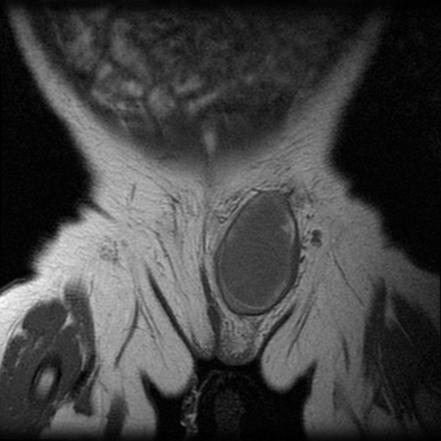

Chiari II malformation

Sagittal T2WI MR shows an inferiorly herniated cerebellar vermis below the foramen magnum, an elongated and flattened 4th ventricle , a low-lying cervicomedullary junction with kinking , an upper cervical spinal cord syrinx , a towering cerebellum , and an enlarged massa intermedia, tectal beaking, stenogyrea (elongated and flattened gyri), dysgenesis fo the corpus callosum

result of myelomeningocele w/CSF loss and ‘sump’ type effect on posterior fossa